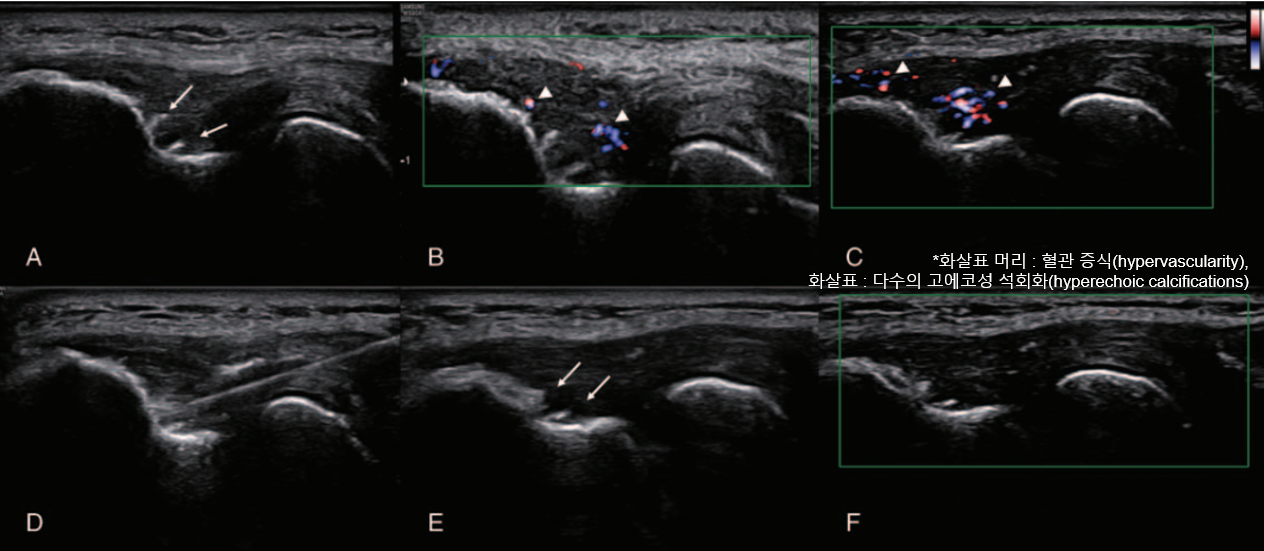

Step-by-step visualization of PDRN injection techniques targeting specific anatomical landmarks—subacromial bursa, common extensor tendon origin, and plantar fascia attachment—translating pharmacologic knowledge into precise clinical interventions.